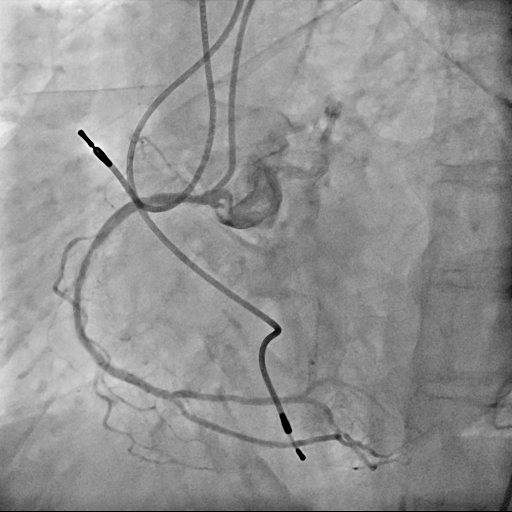

Case was 70's female, and she had a history of paroxysmal atrial fibrillation, chronic kidney disease with hemodyalysis. She was diagnosed with angina pectoris and PCI was performed for RCA ostium with drug-eluting stent. Subsequently, in-stent restenosis was occurred repeatedly. Finally Biolimus-A9 Coated Stent was deployed within the stent, and follow up CAG with coronary angioscopy was performed. ECG showed sinus rhythm with inverted T wave of V1-4, and UCG showed normal LV function.

At the first procedure, underexpanded stent was deployed without debulking for eccentric calcified plaque of RCA ostium lesion. 1 year and 2 months after the initial procedure, in-stent restenosis due to underexpanded stent was occurred. PCI was performed with drug-coated balloon and another 8 months later, re-restenosis with neointima hyperplasia was occurred.

Relevant Catheterization Findings

We used 7Fr JR3.5SH guiding and SION blue ES wire. Wire was easily crossed, and IVUS showed in-stent restenosis with neointimal hyperplasia and underexpanded stent. Long inflation technique using cutting balloon was performed, and Biolimus-A9 coated stent was deployed for in-stent lesion. Post dilation using NC balloon was performed, and procedure was completed. 4 months and 1year and 9 months after the procedure, follow up CAG with coronary angioscopy was performed.

1 year and 2 months after the initial procedure using underexpanded stent for eccentric calcified plaque placed at RCA ostium, in-stent restenosis was occurred. PCI was performed with drug-coated balloon and another 8 months later, re-restenosis was occurred. PCI was performed again with Biolimus-A9 coated stent deployed for in-stent lesion. 4 months, and 1 year and 9 months after the stent implantation, CAG was performed with evaluating coronary angioscopy. At the 4 months later, there was no restenosis and we confirmed beginning of neointima coverage for stent strut. At the 1 year and 9 months later, there was also no restenosis, and we confirmed enough and optimal neointimal coverage as vessel healing after stent implantation. Biolimus-A9 coated stent has early drug release system and polymer-free characteristics. The characteristics of the stent may have contributed to get the early smooth and optimal neointimal coverage, and the prevention of malignant cycle of RCA ostium in-stent restenosis.